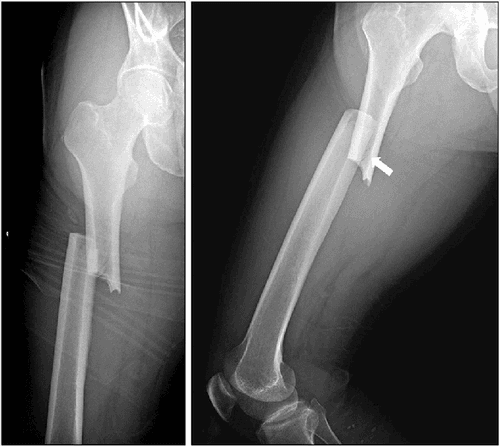

Oblique Fracture - हाडाच्या अक्षावर झालेले फ्रॅक्चर.

Pathological Fracture - आजारामुळे हाडे कमजोर होऊन तुटणे.

Spiral Fracture - हाडाच्या एखाद्या भागाला पीळ पडणे.